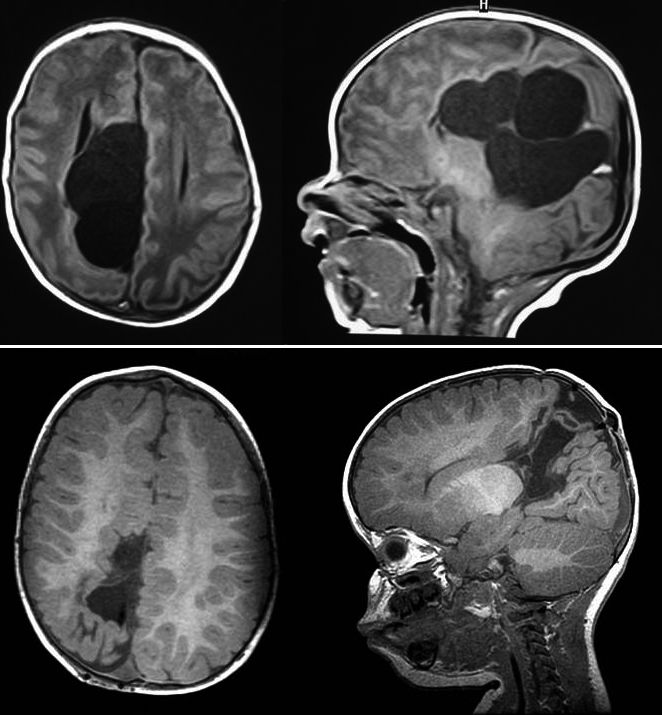

1. Resonancia magnética nuclear (IRM) en los primeros días de vida

2. Clsificación

1. Hemorragia leve Grado I: hemorragia aislada de la matriz germinal.

1. Grado II: hemorragia intraventricular con tamaño ventricular normal. Hemorragia moderada

1. Grado III: hemorragia intraventricular con dilatación ventricular aguda. Hemorragia grave

1. Grado IV: hemorragia intraventricular y parenquimatosa.